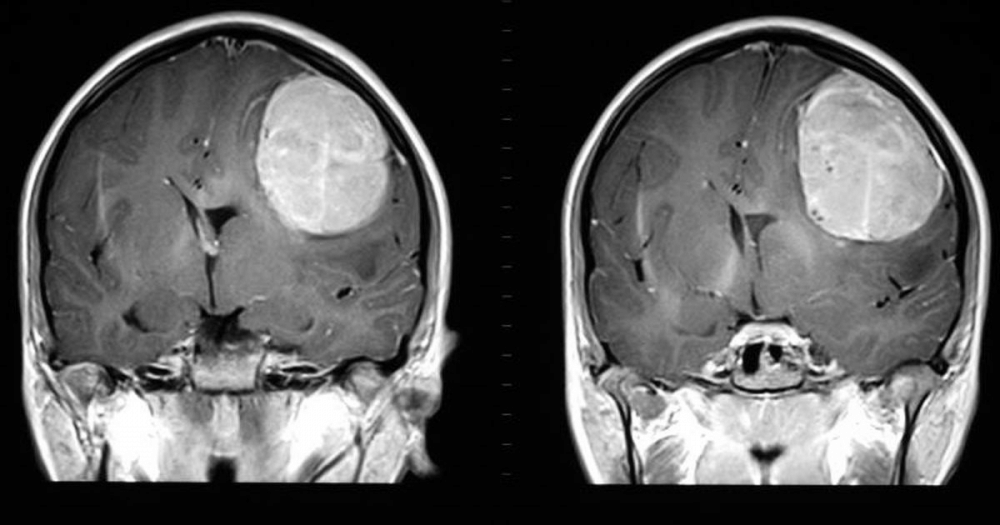

Beberapa waktu lalu publik dikejutkan dengan kanker otak yang dialami oleh Agung Hercules, yang akhirnya merenggut nyawa selebritas yang dikenal berbadan bugar ini. Pasalnya, kanker otak tersebut terjadi secara cepat dan sudah berada di stadium 4! Kanker otak yang dialami oleh Agung Hercules berjenis glioblastoma dan menyerang bagian otak sebelah kiri pada penyanyi sekaligus binaragawan tersebut.

Glioblastoma adalah kanker otak ganas dan sangat invasif yang langka. Terdapat 2-3 penderita glioblastoma dari 100 ribu orang per tahun di seluruh dunia. Penyebab glioblastoma sebagian besar belum diketahui, namun berdasarkan penelitian, 5 persen disebabkan oleh kondisi keturunan dan 95 persen tidak dikaitkan dengan penyebab spesifik apapun, ungkap laman Moffitt Cancer Center.